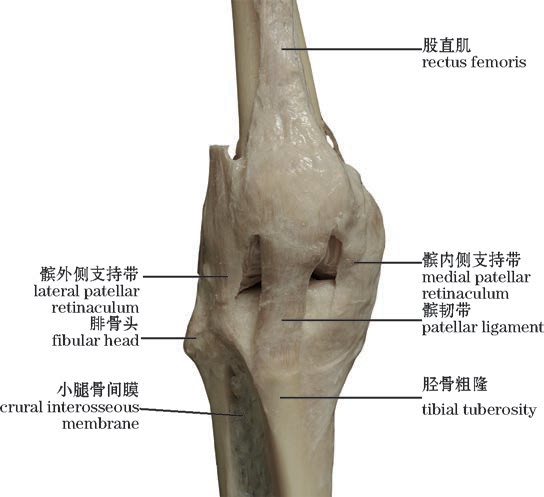

图2-42(2) 膝关节—2(前面观,右)

The knee joint—2(Anterior view,right)